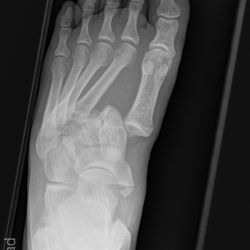

Lisfranc Luxationsfraktur